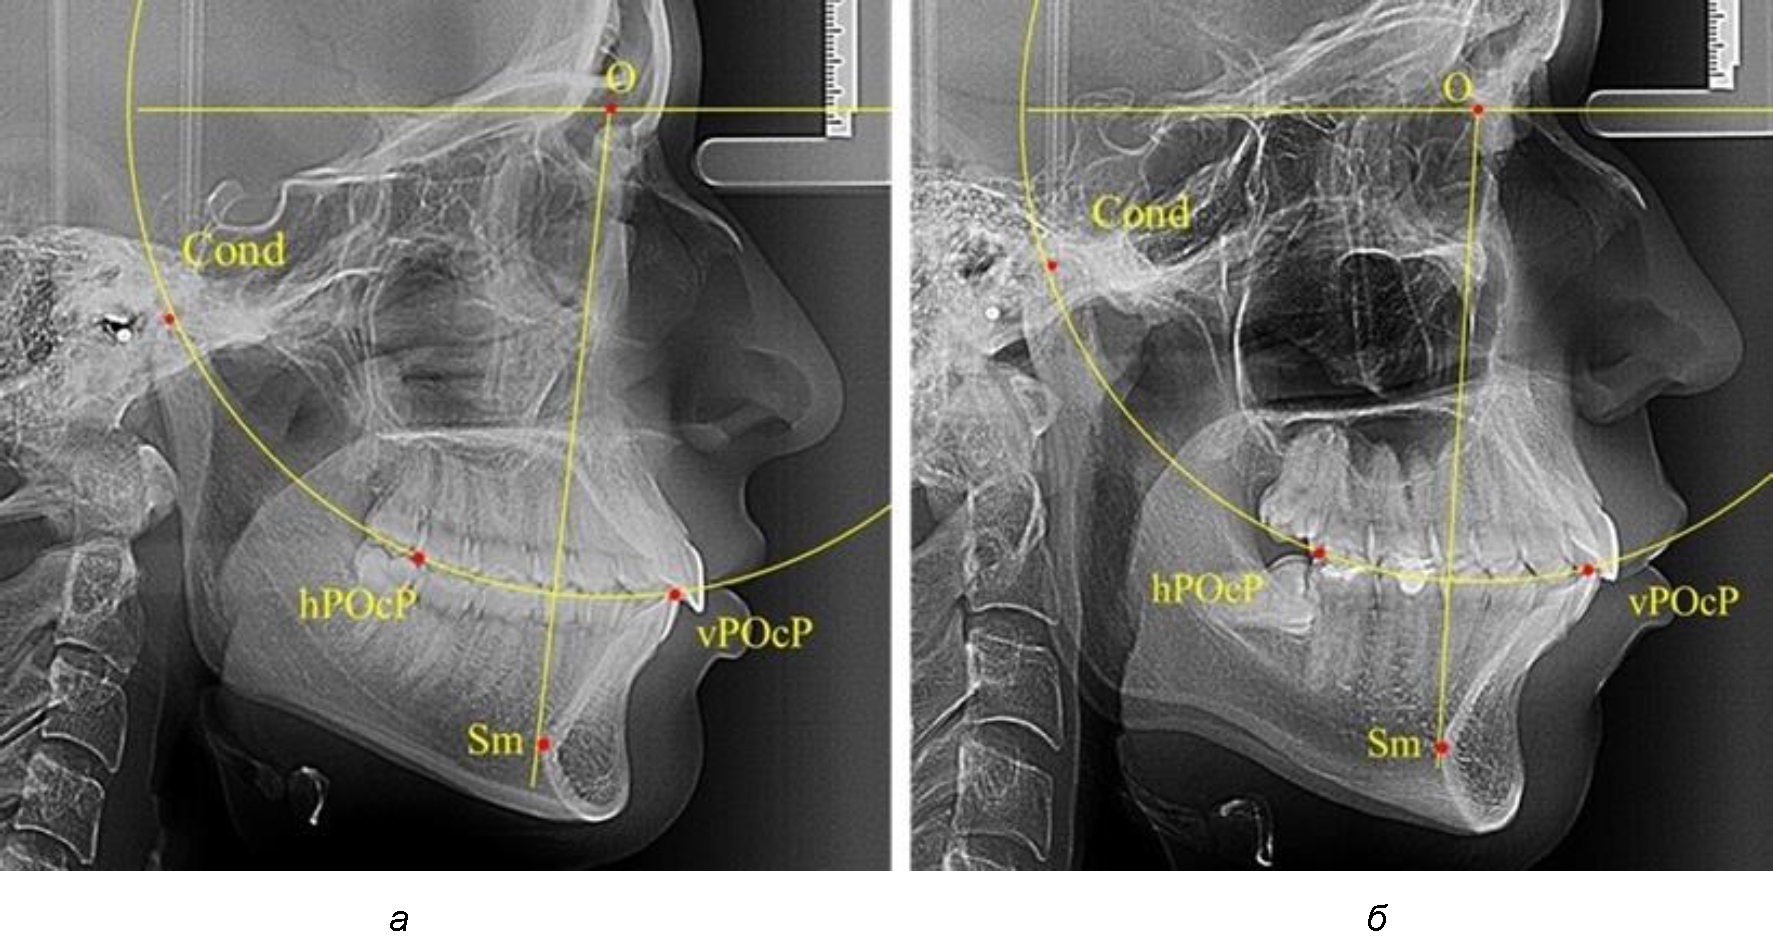

Результаты исследования рентгенограмм с мезотрузионным типом резцов показали, что линия Bimler проходила позади первых премоляров у людей с широким типом подбородочного выступа, однако окклюзия была физиологической и не требовала удаления премоляров, что носило рекомендательный характер при проведении подобных исследований при аномалиях прикуса. У людей со средними формами подбородочного выступа линия Bimler проходила впереди первых премоляров (рис. 2).

Аналогичная ситуация была у людей и с узкими вариантами подбородочного выступа.

Таким образом, при мезотрузионном типе зубочелюстных дуг расположение премоляра впереди линии Bimler при широких вариантах подбородка не может быть критерием выбора экстракционных методов лечения.

Рис. 2. Положение первых верхних премоляров при мезотрузии с широкими (а) и средними (б) размерами подбородка